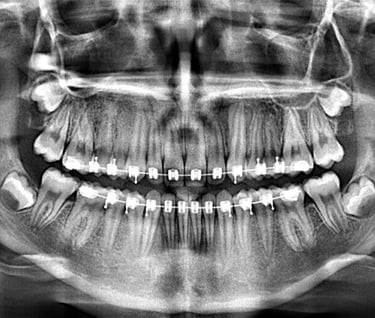

PANORÁMICA DIGITAL

Permite la evaluación de terceros molares, presencia de dientes retenidos, lesiones residuales y restos radiculares, permite ver anomalías del desarrollo, posición, desarrollo y forma de los dientes.

Además, permite ver traumatismos maxilofaciales, y lesiones óseas extensas.